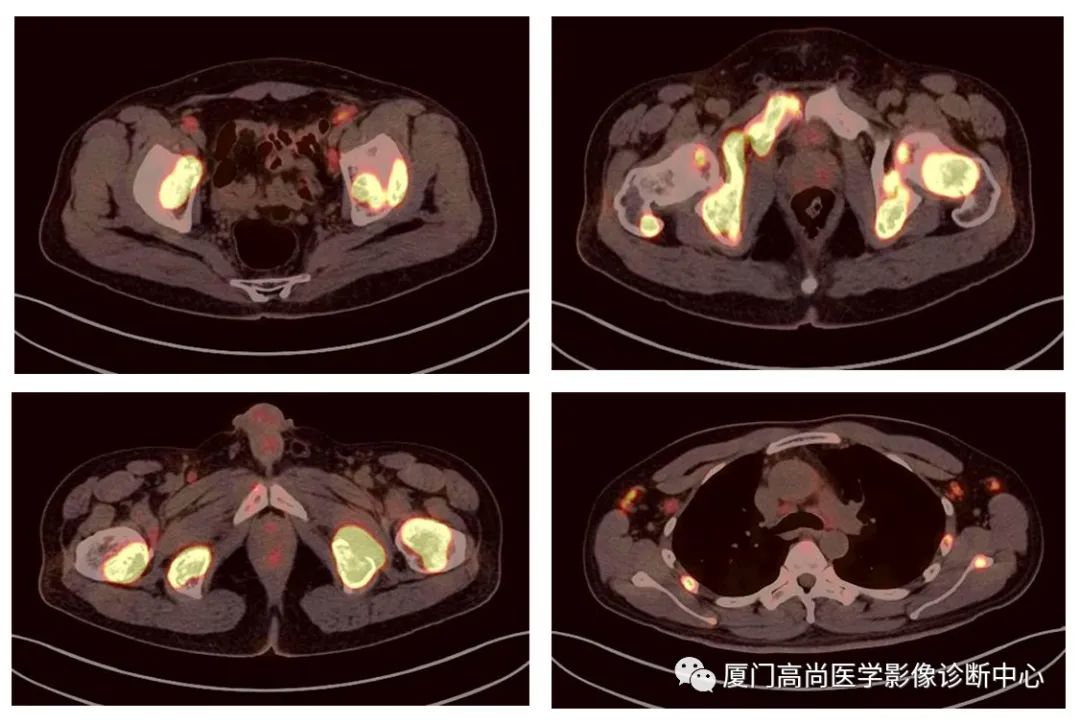

病例1:某男士,36歲,半年前摔傷,當(dāng)時無大礙,近幾個月來腰腿痛,并逐漸加重,消瘦10多斤。MRI檢查發(fā)現(xiàn)腰椎、骨盆 骨質(zhì)異常信號,查血各項腫瘤標(biāo)記物正常,因診斷不清而來做PET/CT檢查

淋巴瘤在骨骼、肝臟、脾臟、淋巴結(jié)表現(xiàn)

肝臟、脾臟、骨骼淋巴瘤病灶

骨骼、腋窩淋巴結(jié)病灶

PET/CT發(fā)現(xiàn) :全身多發(fā)淋巴結(jié)腫大,F(xiàn)DG攝取增高;肝臟、脾臟多發(fā)低密度結(jié)節(jié), FDG攝取增高;雙側(cè)扁桃體腫大,F(xiàn)DG攝取增高;全身多處骨骼破壞,F(xiàn)GD攝取增高;上述考慮為淋巴瘤

經(jīng)淋巴結(jié)穿刺活檢 :病理診斷為彌漫大B細胞淋巴瘤